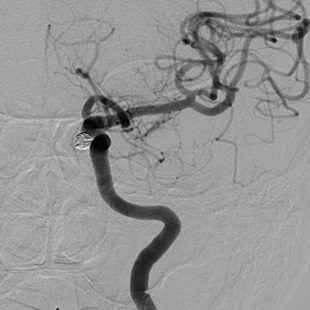

脳動脈瘤に対するコイル塞栓術

瘤内塞栓にて動脈瘤への血流は認めない